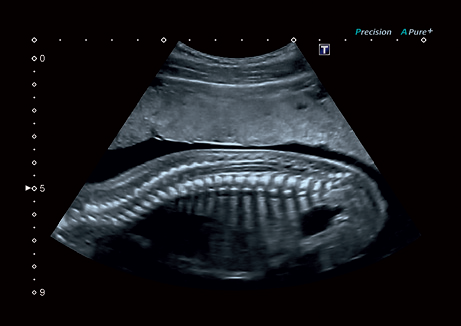

• Precision Imaging - технология получения изображений мелких деталей с четко очерченными границами и высокой однородностью

• Прецизионная визуализация (Precision Imaging) для послойного дифференцирования тканевых структур и высокой детализации;